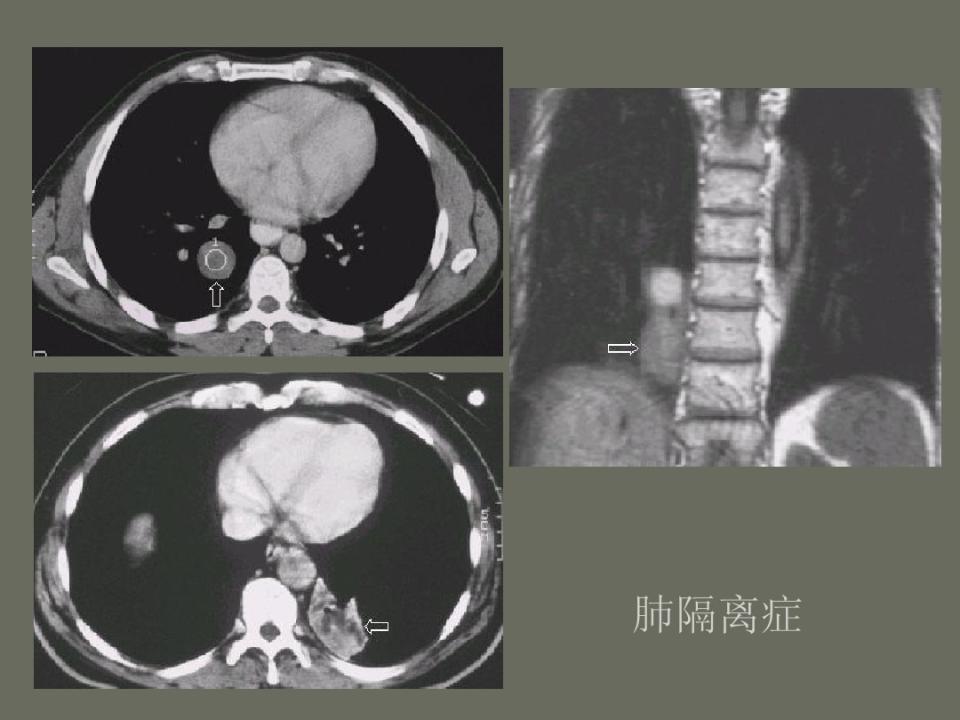

肺部先天性疾病的影像诊断